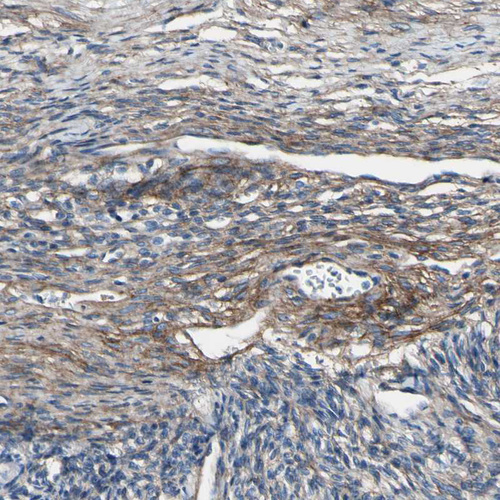

Immunohistochemical staining of human ovary shows moderate cytoplasmic positivity in connective tissues.